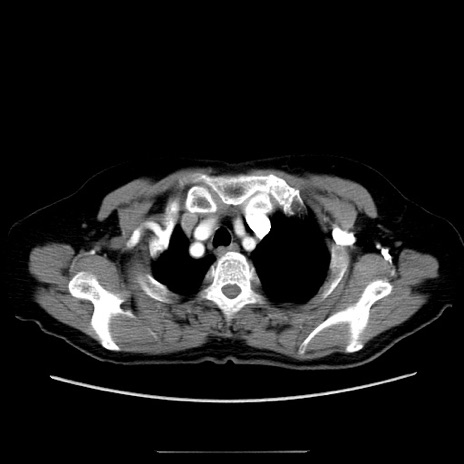

冠状断像

【症例】70歳代女性

【主訴】お腹が張る

【現病歴】1週間くらい前から腹部膨満の自覚あり。昨日夜から増悪したため、本日救急外来受診。

【身体所見】意識清明、BT 36.5℃、BP 165/106mmHg、HR 80bpm、SpO2 98%、腹部:膨満、軟、自発痛・圧痛なし、触診にて不快感あり、腸蠕動音:減弱

【データ】WBC 12600、CRP 1.04